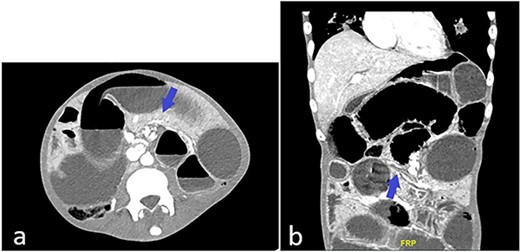

Patient is a frail 28-year-old transgender male to female with poorly controlled human immunodeficiency virus (HIV)/AIDS (CD4 count: 3, HIV viral load: 22000 copies/mL) who presented to the ED with one day of abdominal pain. History was limited as the patient was uncooperative. Vitals on arrival in the ED were: Temp 98°F, Pulse 78, BP 106/55, RR 18, SpO2 97%. The physical exam was significant for cachexia (BMI 17.3), skin changes compatible with skin type Kaposi’s Sarcoma, abdominal distention, and peritoneal signs. Computed tomography (CT) abdomen and pelvis showed multiple dilated small bowel loops with swirling of mesentery (Fig. 1a) and possible transition zone (Fig. 1b).

(a) CT abdomen and pelvis showing possible swirling of mesentery (blue arrow); (b) CT abdomen and pelvis showing dilated and collapsed small bowel loops suggestive of transition zone (blue arrow).